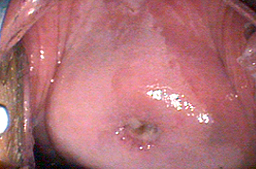

Displasia leve con gran ectropión y lesiones por VPH en vulva.

Tratamiento mediante fotovaporización con láser CO2.

Cicatriazación al mes del tratamiento